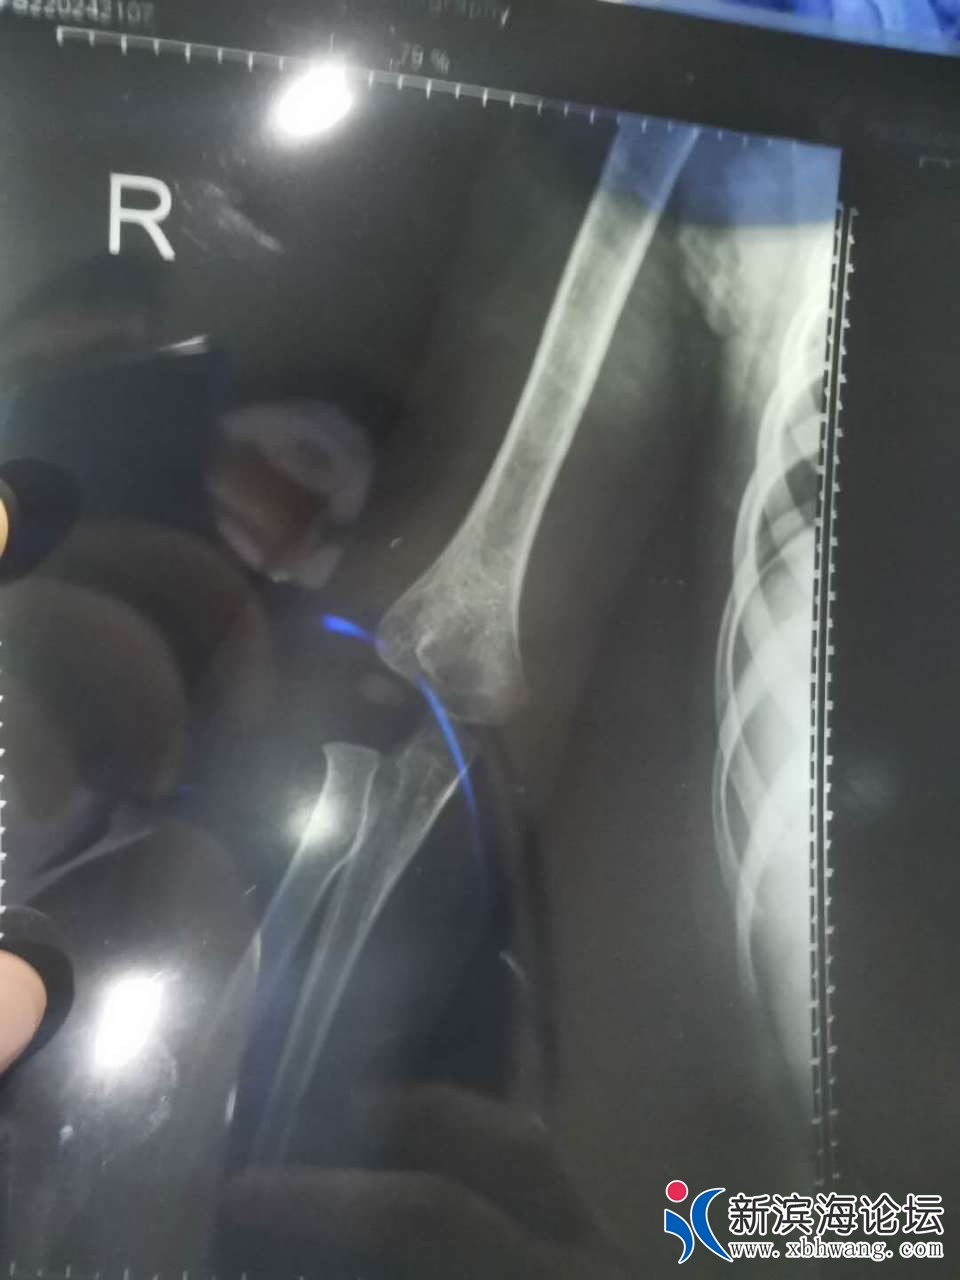

大家好 我是孩子的爸爸   3.31号晚  宝宝不小心从床上摔下来  家人比较担心  就带宝宝来到滨海第一人民医院就诊  挂完号我们等了很久才等到医生过来  简单两句话   就让我们去做血常规  再拍个片子  还嘱咐我们拍完 不用等片子出来   他可以从电脑上看  我们也不懂  就听了医生的话   等医生从电脑上看完片子  告诉我们说宝宝没有什么事  就是有点血肿  让我们回去冰敷一下就可以了  宝宝比较坚强  也没有哭  我们就相信了医生的话  带宝宝回家了  可是再到4.30号总觉得宝宝胳膊使不上力气  再次带着宝宝来到县医院复查  等来的结果却是骨折了  而且还要动手术  我们质疑了  因为3.31号晚上的片子  县医院有3个医生看过  都说没有问题   于是带着之前的片子和5月1号的片子来到其他几个医院   结果给我们的诊断都很肯定宝宝的胳膊骨折了   看过3月31号的片子  也都说  之前的片子就看的出来是骨折了  现在要动手术  而且还担心留下残疾    瞬间就感觉天塌下来了  很相信我们滨海的县级医院   结果给宝宝误诊了   现在已经一个月下来了     宝宝耽误了最佳治疗时期   滨海其他医院已经不接收这么小的宝宝 因为也错过了最佳治疗时间  我们再次来到县医院  想处理下宝宝现在的状况  可是 医院找各种理由  推脱      找到当日的值班医生  现在还不承认  说他没错  还让我们去骨科再看   真就不明白  来到医院  挂号  如果你看不了这个病  为什么让我们去做一系列的检查  还给我们诊断结果  说只是血肿  未见骨折现象     院方一味的找借口推脱  一副天不怕地不怕的样子  你们的良心不会痛吗   你们自己家里没有宝宝吗 以前总是在别人嘴里说县医院太差劲 这次,我们也算是真见到了  庸医  真的是害惨了我们一家人  特别是宝宝  他还4周岁不到  这么小  就遭这么大的罪   还有可能留下残疾的症状     真的就是黑心医院无良医生   也请有关上级领导帮忙彻查此次医疗事故  感谢不尽   下面附上宝宝两次拍的片子  前3张是3.31号晚上的   最后两张是5.1号的

你好,首先感谢你对我院工作的关心和支持,关于你反映的“县医院医生···”一事,我院高度重视,立即组织相关科室调查具体情况,患儿崔某某,男,4岁,因”意外伤"于2020年03月31日晚来我院急诊外科就诊,摄片见肱骨髁旁高密度影,考虑骨骺(小儿肘关节骨骺易与骨折混淆),初诊时不能明确,建议患儿家长三天后至我院骨科门诊复诊,患儿家长因为孩子肿痛不明显,未及时来院诊治,一个月后复查提示肱骨外科骨折,事情发生后,我院已经安排专人对接,目前正与患儿家长商讨下一步诊疗方案。最后再次感谢你对我院工作的关心和监督。